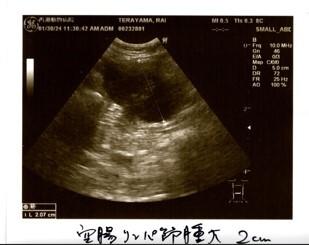

炎症の値は振り切れ、貧血、黄疸、リンパ節腫大、化膿性肉芽腫炎症という検査結果から、FIPを強く疑う。との診断でした。